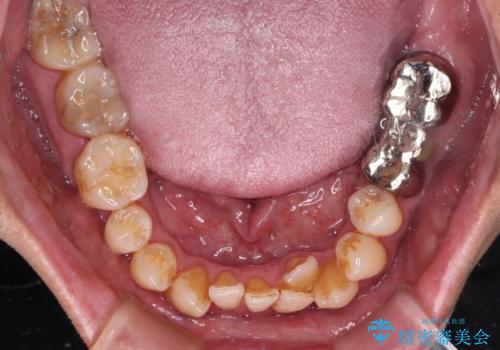

外科手術を併用した矯正治療を検討するほどに隙間の空いた開咬と、顕著な叢生が認められました。

開咬の改善には、舌の突出癖改善のためにトレーニングを行いつつ、インビザラインでの矯正治療が大変有効ですが、上顎骨が下顎骨に対して前方位に位置しており、インビザライン単独で治療を行うよりは補助装置とワイヤー矯正で奥歯の咬み合わせを改善してから、開咬改善のためのインビザライン矯正治療を行うこととしました。

奥歯の銀歯は、土台の一部に抜歯が必要であったので、矯正治療の途中で抜歯してからオールセラミックブリッジによる補綴治療を行うこととしました。